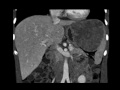

Sclerosing angiomatoid nodular transformation (SANT) of the spleen

Incidentally discovered splenic mass lesion. MR images demonstrate a large T2 hypointense mass arising from the spleen with restricted diffusion. CT images demonstrate a large, milyl heterogeneous mass arising from the spleen. This was found to represent sclerosing angiomatid nodular transformation (SANT) of the spleen after surgery.